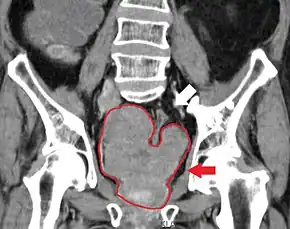

Imaging

Ultrasound and magnetic resonance imaging (MRI) are the two main imaging methods used for prostate cancer detection.

-

MRI Organ-confined prostate cancer -

Bony metastases from prostate cancer

MRI

On MRI, the central and transitional zones both have lower T2 signal than the peripheral zone. Since the central and transitional zones cannot be distinguished from each other, they can be best described as the central gland on MRI. Thus, the peripheral gland has a higher signal on T2WI than the central gland. In the peripheral gland, prostate cancer appears as a low-intensity lesion. However, in the central gland, low-intensity lesions cannot be distinguished from the low-intensity central gland. Diffusion restriction is instrumental in identifying and characterizing central gland lesions. Lymphadenopathy can be seen best on postcontrast, fat-suppressed T1WI.

Other regions can be described on MRI. The anterior fibromuscular stroma and the prostate capsule along the posterior and lateral prostate have a low T2WI signal, in contrast with the bright signal of the peripheral zone. Extraprostatic extension can be seen with disruption of capsule integrity.

As of 2011, MRI was used to identify targets for prostate biopsy using fusion MRI with ultrasound (US) or MRI-guidance alone. One study reported that given a clinical suspicion, MRI-guided fusion biopsy detected clinically significant cancer in 38% compared to 26% in the standard biopsy group.[75] In candidates for active surveillance, fusion MR/US-guided prostate biopsy detected 33% of cancers compared to 7% with standard ultrasound-guided biopsy.[76]

The prostate imaging-reporting and data system defines standards of clinical service for multiparametric MRI (mpMRI), including image creation and reporting. PI-RADS version 2 scoring has shown a specificity and sensitivity of 73% and 95%, respectively, for detection of prostate cancer.[77]

Prostate MRI is also used for surgical planning for robotic prostatectomy. It helps surgeons decide whether to resect or spare the neurovascular bundle, determine return to urinary continence, and help assess surgical difficulty.[78] MRI can also be used to target areas for research sampling in biobanking.[79][80]